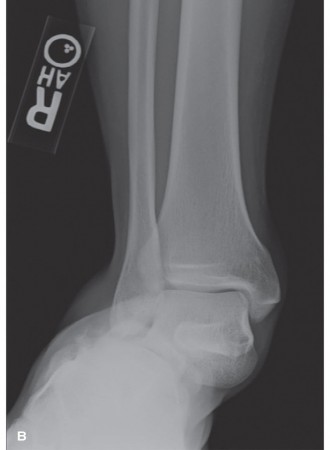

Standard Radiographs:

- Anteroposterior (AP), lateral, and mortise views of the affected ankle.

- Full-length tibia/fibula views to rule out proximal fibula fractures (Maisonneuve injury) in cases of syndesmotic disruption.

Computed Tomography (CT) Scan:

- Strongly recommended for complex fracture patterns (e.g., trimalleolar, pilon fractures) to delineate articular involvement, fracture comminution, and the presence of osteochondral fragments.

- Highly valuable in identifying potential soft tissue interposition pre-operatively, though EDB interposition might not always be clearly evident.

- Provides a 3D understanding of the deformity and helps plan implant placement.